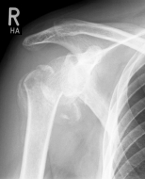

Fracture prostheses for complicated humeral head fractures

left: X-ray of a humeral head fracture before treatment with a fracture prosthesis.

right: X-ray of a humeral head fracture after treatment with a fracture prosthesis